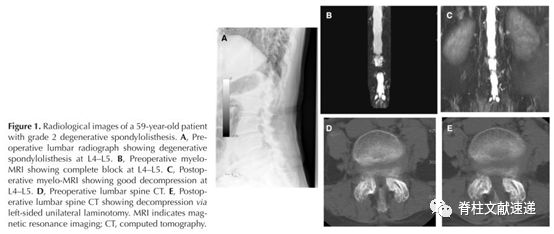

典型病例:图1显示一例59岁L4/5二度退行性滑脱患者:术前腰椎X线片(A)、术前和术后L4/5水平MRI扫描(B, C)、术前和术后CT断层扫描(D、E)。左侧椎板切除+双侧减压,术后随访5年,结果良好。